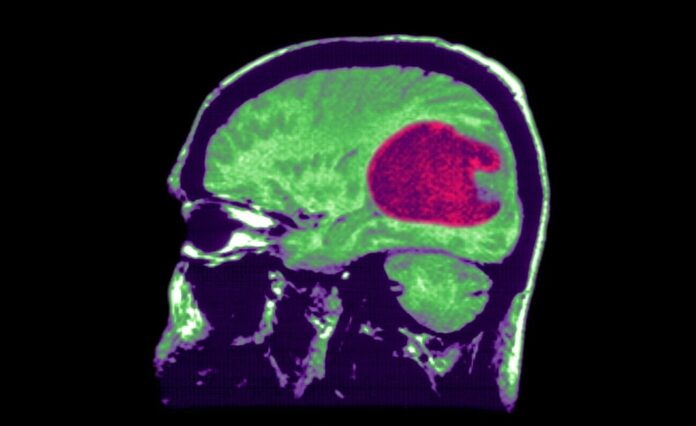

Yapay Zeka, en yaygın beyin tümörü olan gliomaların analizine yardımcı olabilir ve hastaların ameliyathanede geçirdikleri süreyi azaltabilir.

Sinirbilim araştırmacıları, beyin tümörü için kullanılan gliomları çözmek için onlarca yıldır mücadele ederken, Harvard Üniversitesi Tıp Fakültesi’nden bilim insanları, üretilen yeni bir yapay zeka aracının, beyin tümörlerinin tedavisine yardımcı olabileceğini duyurdu.